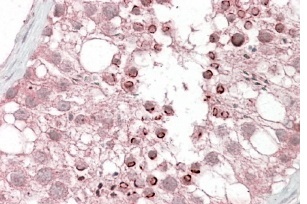

Supportive validation

- Submitted by

- Aviva Systems Biology (provider)

- Main image

- Experimental details

- OAEB00679 (3.8µg/ml) staining of paraffin embedded Human Testis. Steamed antigen retrieval with citrate buffer pH 6, AP-staining.

- Sample type

- Human Testis lysate

- Primary Ab dilution

- 3.8 µg/mL